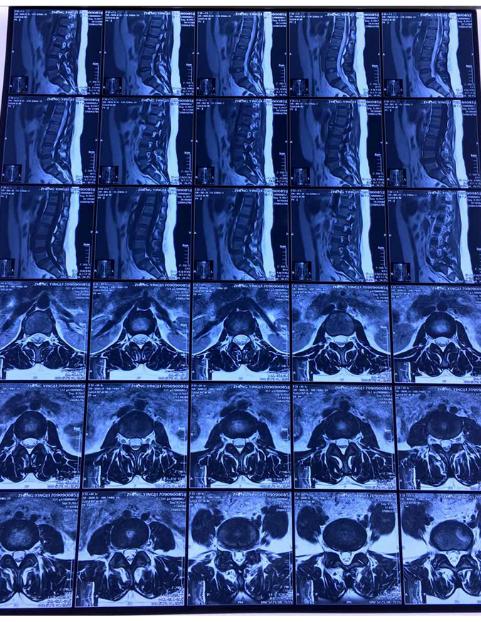

影像资料

从影像资料可以看到腰5峡部裂造成腰5骶1滑脱,滑脱有Ⅰ度。患者双侧峡部裂,也就是是由于腰部突然受力等原因导致左右两侧的椎弓峡部都断裂,但是患者只有三十多岁,比较年轻,肌肉力量比较强,避免断裂后继续向前滑移。

临床上,患者在做影像检查的时候会在站位和坐位出现明显的不同。比如这位患者核磁和CT是躺下来拍的,侧位平片是站立时拍的或卧位(但是时间较短)明显可以看到侧位平片显示的滑脱更严重。那么,腰椎滑脱该怎么判断已经发展到几度了呢?一般来说,患者在出现症状以后到医院做检查,此时如果做站立位腰椎侧位平片,可以明确滑脱的程度。